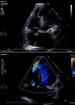

Modified 2-dimensional (top) echocardiogram and color flow Doppler image (bottom). Apical 4-chamber views show a breach in the interventricular septum and free communication between ventricles through a large apical septum ventricular septal defect in a patient who recently had an anterior myocardial infarction.